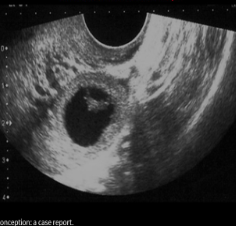

USA ectopic pregnancy

Complex adnexal mass located between ovary and UT

Fetal heart motion may be seen

Adnexal tubal ring (bagel or donut sign)

RING OF FIRE (increased vascularity surrounding decidual reaction)

Ectopic